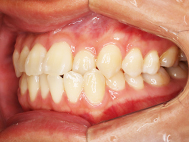

After

| 症状 | 上下前歯叢生 |

| 治療内容 | 上顎部分裏側矯正 下顎は目立ちにくい透明な装置 |

| 治療期間 | 11ヶ月 |

左上の前歯内側に入っている下の前歯ガチャ歯

左上前歯が下の歯の内側に入っているのが気になるとの事で来院されました。目立たない矯正治療を希望しているとのこでした。 上顎の装置は、歯の裏側(リンガル装置)で下顎は表側で矯正治療を行いました。口を閉じた時、上の前歯が内側に入っている為に下の歯を前に押し出している状態でした。その為、上の歯を前に出すだけではその歯が下とのかみ合わせの関係で、前に飛び出すような治療となってしまいます。 今回の症例ではシュミレーションを見て頂き、下の歯も治療し、内側へ下げることによって上の歯も飛びだすことなく、キレイにおさまることを説明し、上下一緒に矯正することをお勧めさせて頂きました。